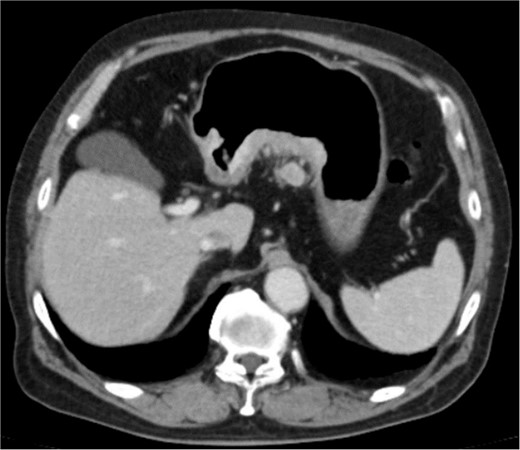

The amylase levels of drainage fluid and blood at postoperative day (POD) 1 (Ascites 6980 IU/dl, Serum 1123 IU/dl) and POD 3 (Ascites 673 IU/dl, Serum 487 IU/dl) revealed pancreatic fistula based on the criteria of International Study Group of Pancreatic Fistula [2]. After that, their results improved, and fluoroscopy showed no stenosis and leakage. Therefore, we removed all drains at POD 8, however the following day, the patient developed high fever. Plain CT revealed intraperitoneal fluid around subdiaphragmatic and duodenal stump (Fig. 3). We inserted a pig-tail drainage tube to the subdiaphragmatic space (Fig. 4). Since biliary fluid was discharged through the tube, we suspected duodenal leakage and started infusion of somatostatin analogs and antibiotics. At POD 13, the patient complained of whole abdominal pain with peritoneal signs. As the patient became hemodynamically unstable, we performed emergent laparotomy to lavage and insert multiple drainage tubes. Two perforation pinholes were identified in the anterior wall of the duodenum, near the stump. We resected the vulnerable duodenal stump including the perforation site and closed by Gambee’s method with unabsorbable 4–0 proline (Fig. 5). We inserted multiple drainage tubes (Fig. 6a): a C-tube from the cystic duct into the common bile duct to separate biliary juice and pancreatic juice, a dual drainage tube around the duodenal stump with continuous suction (Fig. 6b), a simple intraluminal drainage tube via the duodenum near the stump through a new skin incision on the left side of the abdomen for duodenal decompression, and a drainage tube into the rectovesical pouch. After the reoperation, we irrigated the cavity around the duodenal stump through each drain with saline. Since the contrast agent did not flow into the duodenum and the cavity around the duodenal stump gradually got smaller (Fig. 7), oral intake of fluid diet was initiated at POD 37. However, fistulography at POD 44 showed that the fistula of duodenal stump had relapsed (Fig. 8). Although we considered performing second reoperation for duodenal stump closure, due to the cavity around the duodenal stump was located, we continued conservative management and irrigation via drainage tubes. Fistulography demonstrated no leakage from the duodenal stump at POD 56, and the patient discharged at POD 59.

Diagnosis of postoperative duodenal perforation. CT showed ascites in subdiaphragmatic space (arrow) and around duodenal stump (circle) at POD 8.